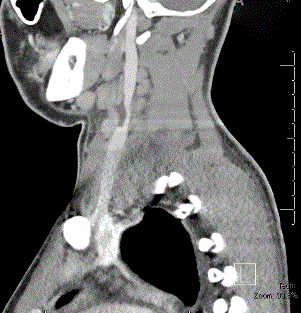

On admission, Clindamycin was started for the concern of a pulmonary abscess until gram stains on the blood cultures grew Gram Negative and Gram Positive Rods. The patient was then converted to Ceftazidime, to cover possible pseudomonas, and Vancomycin, for possible MRSA. Over the next day, he continued to have significant right sided chest pain and persistent leukocytosis, fevers, and oxygen requirement. A repeat CXR was obtained on his third day of admission which showed a large right sided pleural effusion (Figure 3). Blood cultures at this time came back positive for Fusobacterium necrophorum which raised immediate concern for Lemierre’s syndrome. He was restarted on IV Clindamycin and a CT larynx and chest was obtained, showing a possible non-loculated empyema, worsening infectious pneumonia, a clot in the left internal jugular vein, but no retropharyngeal abscess. (Figures 4 and 5). The Cardiothoracic surgery team was consulted and the patient went for right sided Video Assisted Total Decortication. They were able to peel off an exudate made up of fibrinous material with focal granulation tissue surrounding the lung and then drain the fluid. He had 3 chest tubes to drain fluid over the next few days, and was discharged on post-op day 5. On follow-up 2 weeks later, he was still on clindamycin and was feeling better, with no fevers and much improved breathing. During admission, the allergy/immunology team found he did not have a true penicillin allergy.

Figure 3. CXR